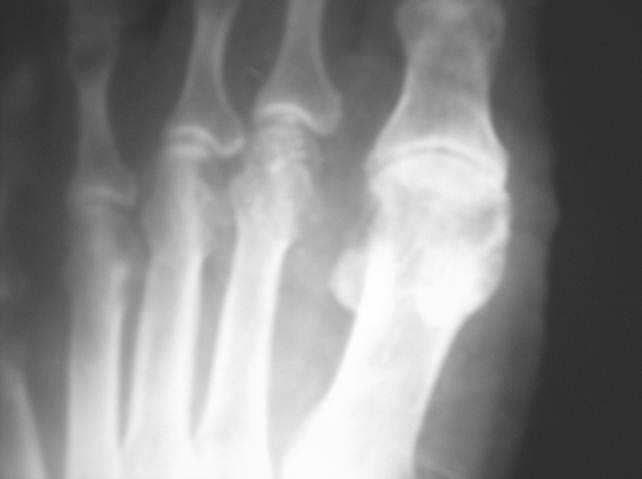

gout